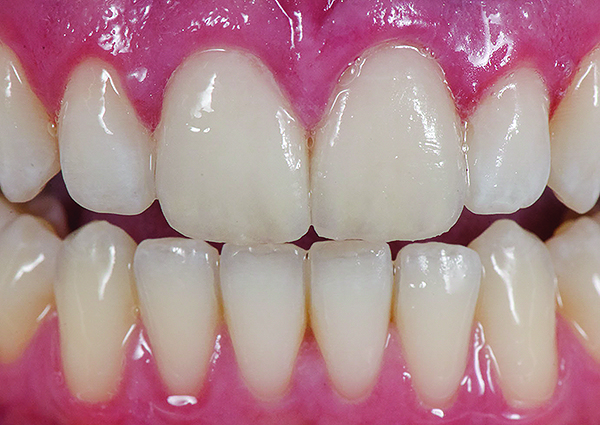

Fig 1. Preoperative (Fig 1), preparation (Fig 2), and final postoperative (Fig 3) images of a two-unit CL-I feldspathic veneer case.

Figure 1

Fig 2. Preoperative (Fig 1), preparation (Fig 2), and final postoperative (Fig 3) images of a two-unit CL-I feldspathic veneer case.

Figure 2

Fig 3. Preoperative (Fig 1), preparation (Fig 2), and final postoperative (Fig 3) images of a two-unit CL-I feldspathic veneer case.

Figure 3

Class I (CL-I) powder and liquid porcelains are created from materials primarily containing silicon dioxide and possess a glassy matrix and varying amounts of a crystalline phase within the glassy matrix (eg, Creation Porcelain, Jensen Dental, www.jensendental.com; Ceramco 3, DENTSPLY International, www.dentsply.com; EX-3, Kuraray Noritake Dental, Inc., www.kuraraynoritake.com). The CL-I group includes feldspathic porcelains, referred to as such because they were originally—and some continue to be—made from naturally occurring feldspars (ie, aluminosilicates composed of assorted quantities of potassium, sodium, barium, or calcium).9,17 Several feldspathic material options are available on the market today (eg, VITA VM 13, VITA Zahnfabrik, www.vita-zahnfabrik.com; Vintage Halo, Shofu, www.shofu.com) (Figure 1 through Figure 3).

CL-I materials are fabricated by hand (Figure 4); they are the most conservative and generally the most translucent ceramic materials, but they are also the weakest.9,10,18 The material’s high translucency and esthetics create the illusion of natural teeth.9 Powder/liquid porcelain materials are ideal for cases in which significant enamel remains and/or there is healthy tooth structure on the teeth (ie, 50% or more remaining enamel on the tooth), and 50% or more of the bonded subst rate is enamel, and 70% or more of the margin is in the enamel. Feldspathic porcelain restorations that are bonded to primarily enamel substrates have proven to be highly successful long term.19

Powder/liquid porcelains demonstrate high esthetics and workability, and because they can be layered very thinly and placed directly on the enamel, they are considered the most conservative of the metal-free ceramic classes.10 CL-I porcelains require a thickness of 0.2 mm to 0.3 mm for each shade change.20,21

This class of materials is generally indicated for anterior restorations but can also be used for the occasional bicuspid and rare molar, providing all parameters are at a very low risk level (Figure 5 and Figure 6).